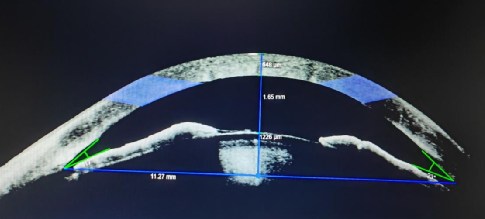

左眼术前前节OCT:左眼前房深度1.65mm(正常成年人为2.5—3.0mm)